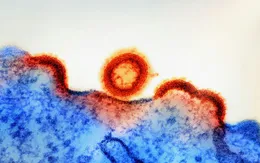

Báo động tình trạng lây nhiễm HIV/AIDS ở Philippines

VTV.vn - Philippines đang đối mặt đợt gia tăng mạnh các ca nhiễm HIV/AIDS, với mức độ lây lan nhanh nhất khu vực châu Á - Thái Bình Dương.